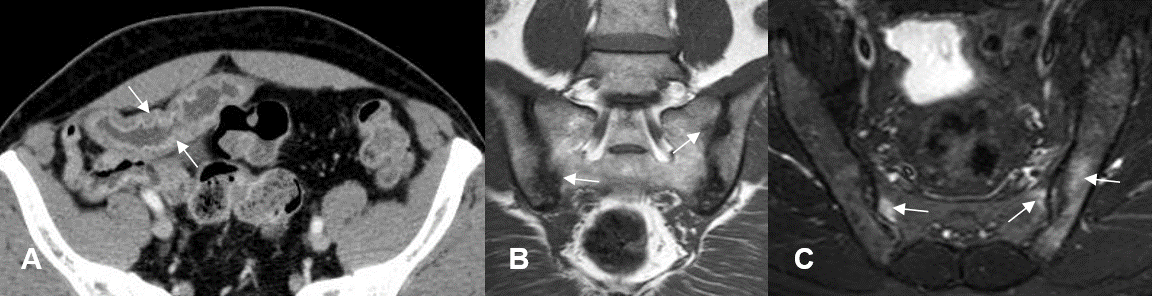

Fig 12. Sacroileitis Subaguda.

A: Rx Pelvis AP. Esclerosis en el componente iliaco derecho.

B: RM T1 coronal y C: RM T2 axial. Osteitis de los componentes sacro e iliaco, hiperintenso en ambas secuencias, por evolución subaguda. (Flechas).